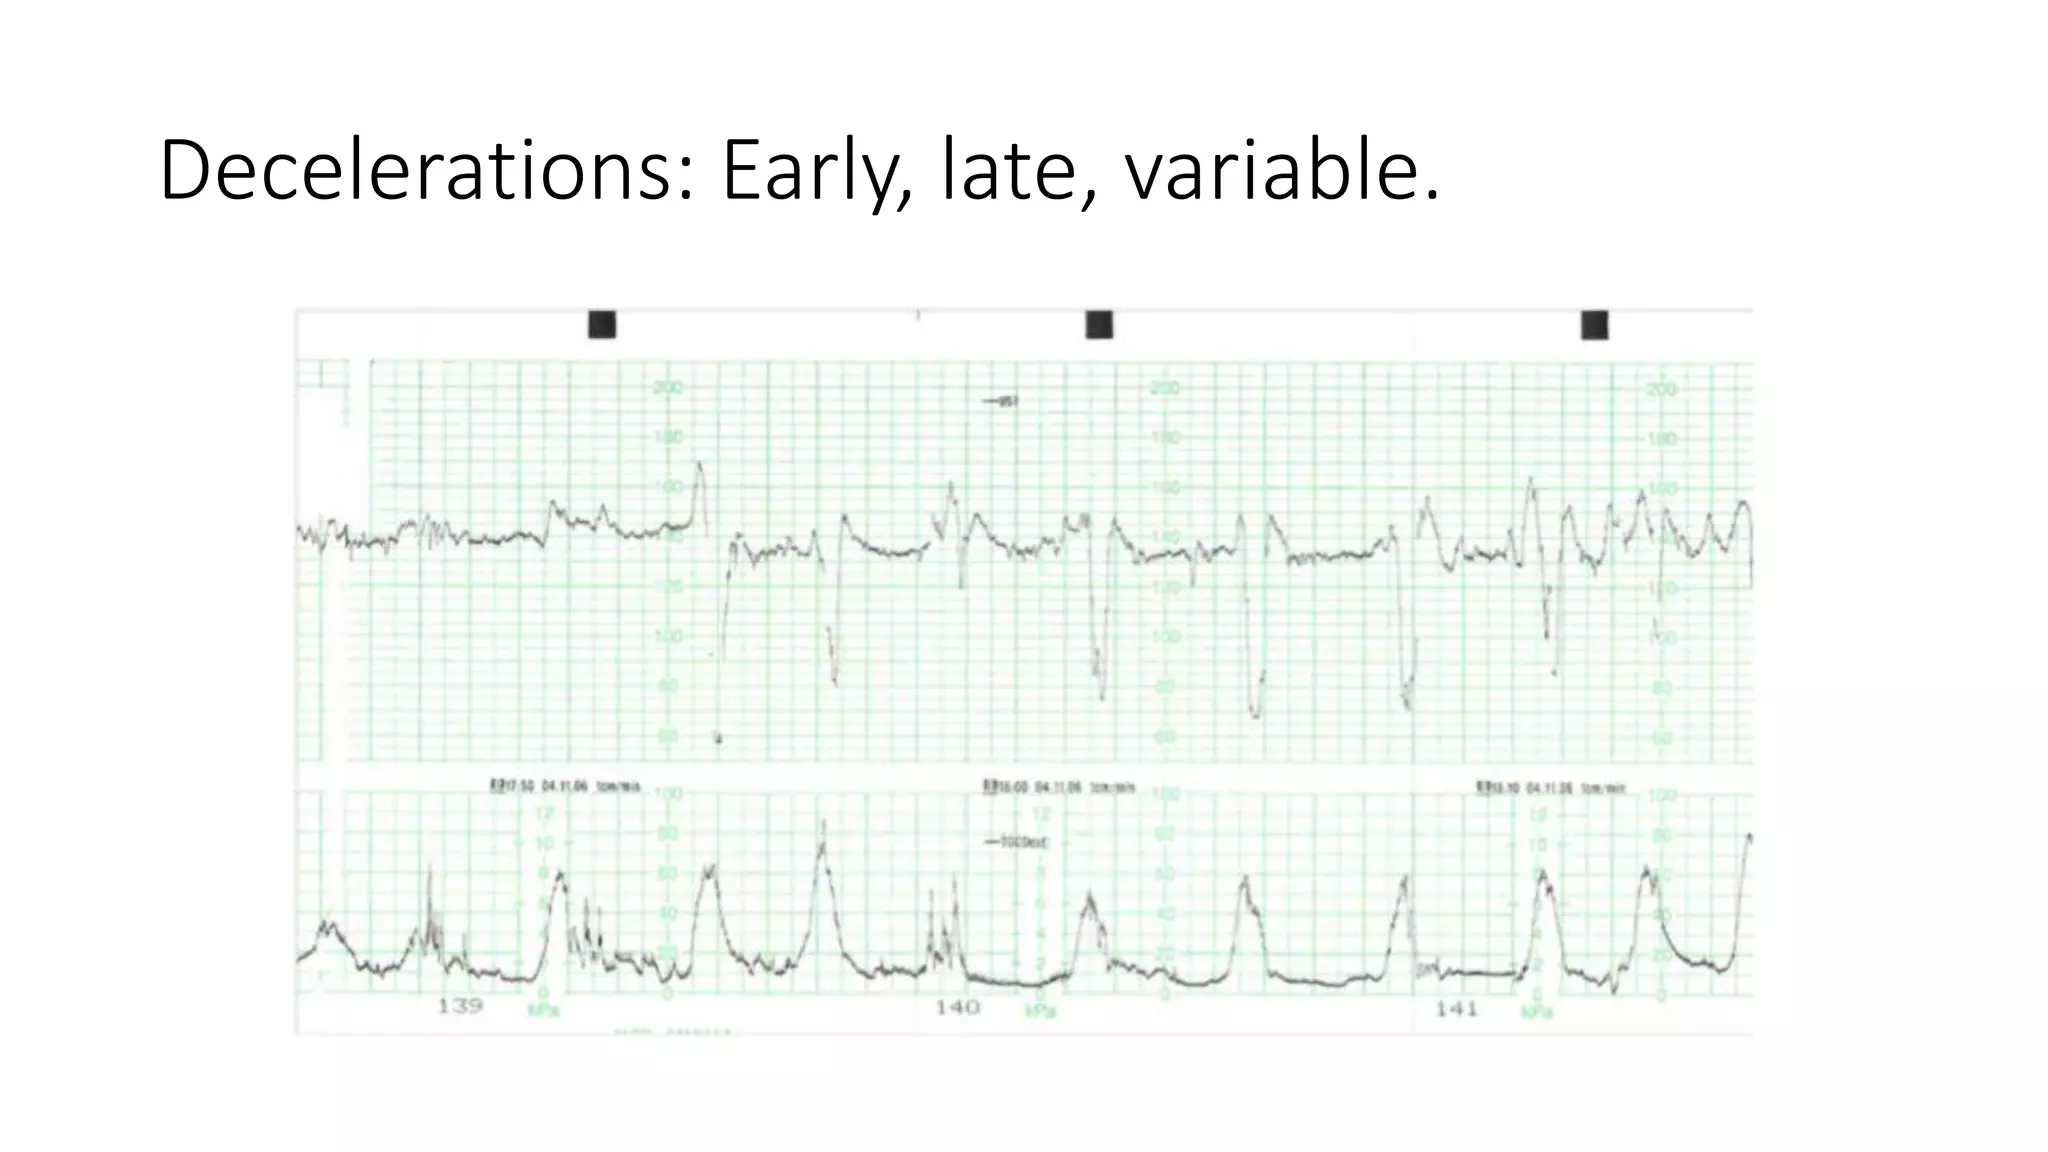

The document discusses key metrics for monitoring a baby's heart rate in utero, including the normal baseline rate of 100-160 bpm and variability. It also covers types of accelerations and decelerations that can occur, such as early or late, as well as bradycardia, which is an abnormally slow heart rate.